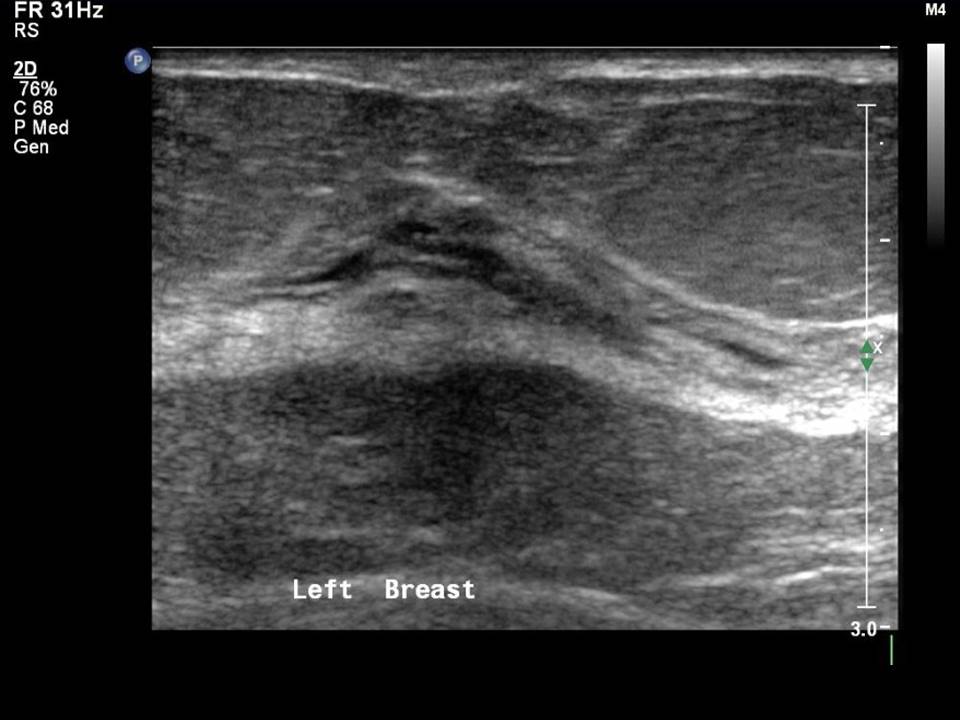

From www.uclahealth.org

Basics of Breast Ultrasound Radiology UCLA Health What Does Echotexture Mean This refers to the brightness of the tissue. It can be caused by inflammation, fibrosis, cysts, tumors, or scarring, and. Echotexture refers to the visual representation of the liver’s ultrasound image. What do results from a liver ultrasound mean? Morrey's the elbow and its. Echotexture or echopattern describes the ultrasound appearance of the uterus. Mccomb] a liver is described as. What Does Echotexture Mean.

From www.slideserve.com

PPT BREAST SONOGRAPHY PowerPoint Presentation ID1189900 What Does Echotexture Mean It can be caused by inflammation, fibrosis, cysts, tumors, or scarring, and. Coarse echotexture, marked by increased sound scattering, indicates underlying liver disease. This refers to the brightness of the tissue. Echotexture refers to the visual representation of the liver’s ultrasound image. Echotexture or echopattern describes the ultrasound appearance of the uterus. Various conditions lead to coarse. What do results. What Does Echotexture Mean.